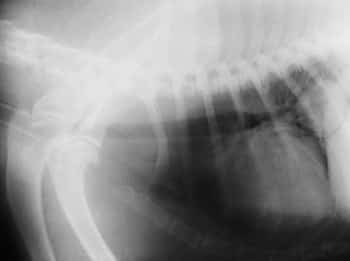

Lulu had 4 different chest xrays taken today under a general anesthetic (to ensure she didn’t move – which would cause a blurred image). The xrays revealed a large abnormal mass in the lung.

Please have a look at the xray from today below (the quality isn’t as good as I took a photo with my digital camera)! Can you spot the mass? The heart here is definitely bigger than usual. We measure the heart a special way by adding the width and height compared to the vertebrae above the chest (the thoracic vertebrae). This gives us a special score (the VHS – vertebral heart score) that allows us to assess the heart size of ALL breeds of dogs. Lulu definitely has heart enlargement which could be contributing to her cough – and so she will be sent for an echo (ultrasound of the heart) very soon.

Did you find the mass? Do you know what end of the picture the head would be? Where is the trachea (windpipe)? Have a look at the image below for more help! (Sorry! I had to use ‘paint’!)

If you switch between the two images you can very easily spot the abnormal mass up behind the heart. This area is usually approximately the same black color that you can see to the left of the heart. The question is – what is this mass? Is it a tumor? It is a localized infeciton (aka – an lung abscess)? The mass was visible in the same spot in all four xrays confirming it’s place within the chest in a certain part of the lungs – the right caudal lung lobe. Given lulu’s age and how the mass looks on the xray – it is very much likely that this a tumor. Even if this is the case – there are even more questions to ask! Is this a primary lung tumor (did it start in the lungs?) or is it a secondary lung tumor (is there a tumor somewhere in the body that has metastasized (spread) to other parts of the body,